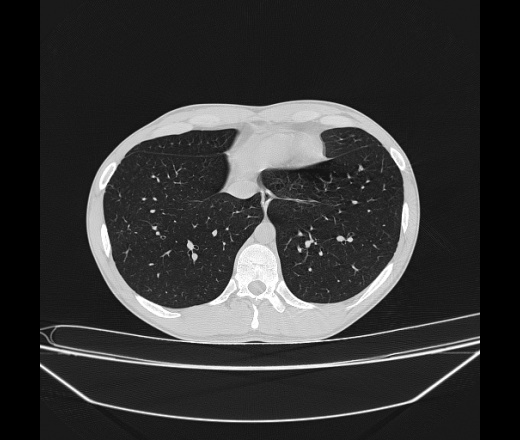

Молодой парень 18 лет, призывник, при прохождении ФЛС на верхушек левого легкого выявили очаги средней интснисвности с нечеткими контурами, тяжи. Сделали бок и томограммы 6-7-8. Везде описывают как очаговый твс. Вижу только перибронхиальный фиброз. Что за изменения в бронхах, указано нижи стрелками, тоже перибронхиальный?

Не стал бы говорить об очагах. Акцентировал бы не на фиброзе, а на тракционных бронхоэктазах. Не обязательно они результат tbc бронхов, но проверить не помешает.

Иван, пациент ведь уже "направлен с ОПТД", так?surprise Возвращайте его назад с заключением о возможном микобактериозе. Остаточные поствоспалительные ( посттуберкулёзные?) в дифряд.Очаговый твс с неясной активностью они уже себе "нарисовали", как я поняла.